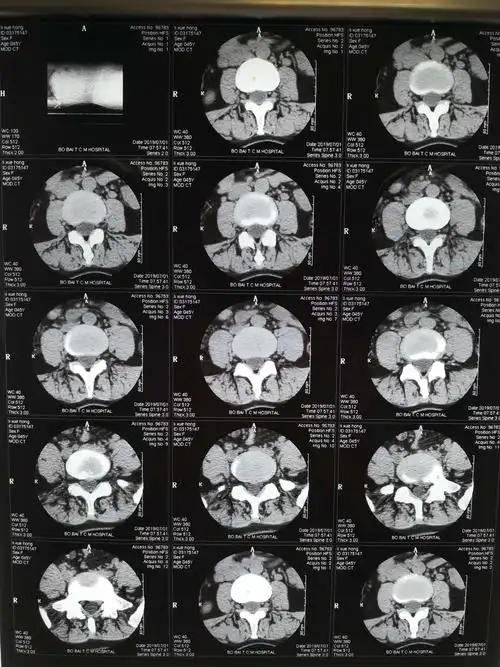

腰椎ct提示腰5/骶1椎间盘向左侧突出